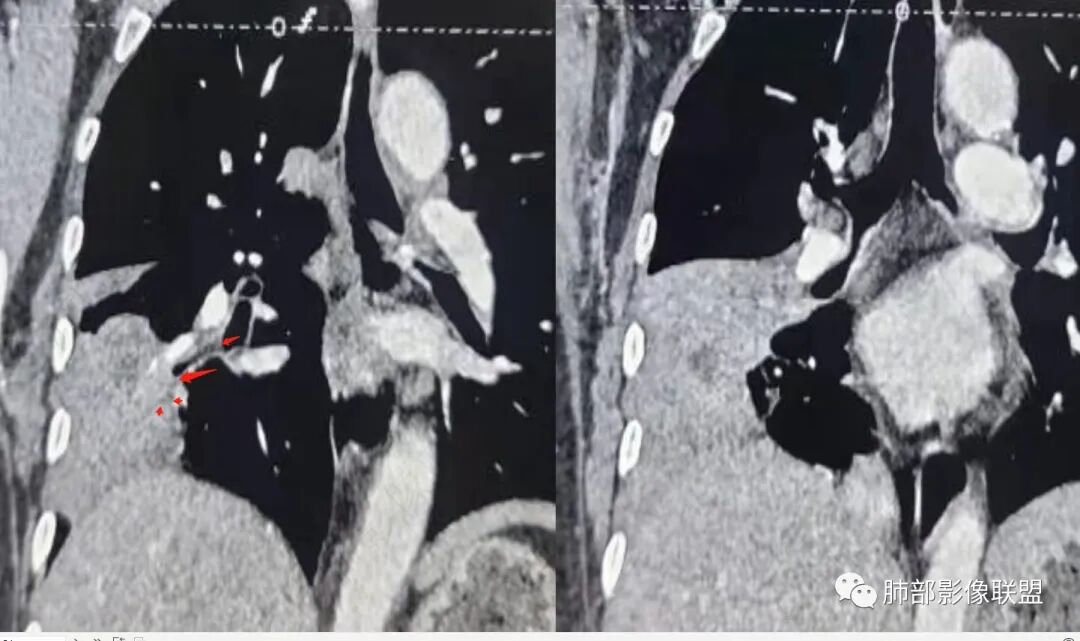

这应该是支气管腔内粘液栓

右中叶支气管

下叶前基底段支气管

这个病灶中叶、下叶都有

坏死腔是连通的

这个支气管局部堵了,但是远端支气管走形自然,腔内粘液栓

这个病例,看长轴、形态,首先跨叶,里面的坏死腔,它是相通的,就是跨中叶及前基底段。

看中叶外侧段的病变,我观察到支气管与坏死腔相通的,支气管这种堵塞就不踏实了,假如是腔内的病变,就不太支持。

如果是腔内的病变,第一,应该是局限在某个叶的,不可能上下叶都有。所以不太支持腔内的病变。因此考虑腔外的病变。腔外局限的肿瘤肯定不符合,假如这个病灶是个局限大肿块的话,里面肺动脉走势还可以。

然后中叶与下叶的坏死腔病灶是相通的,病灶是跨叶的,胸膜糊墙为主。